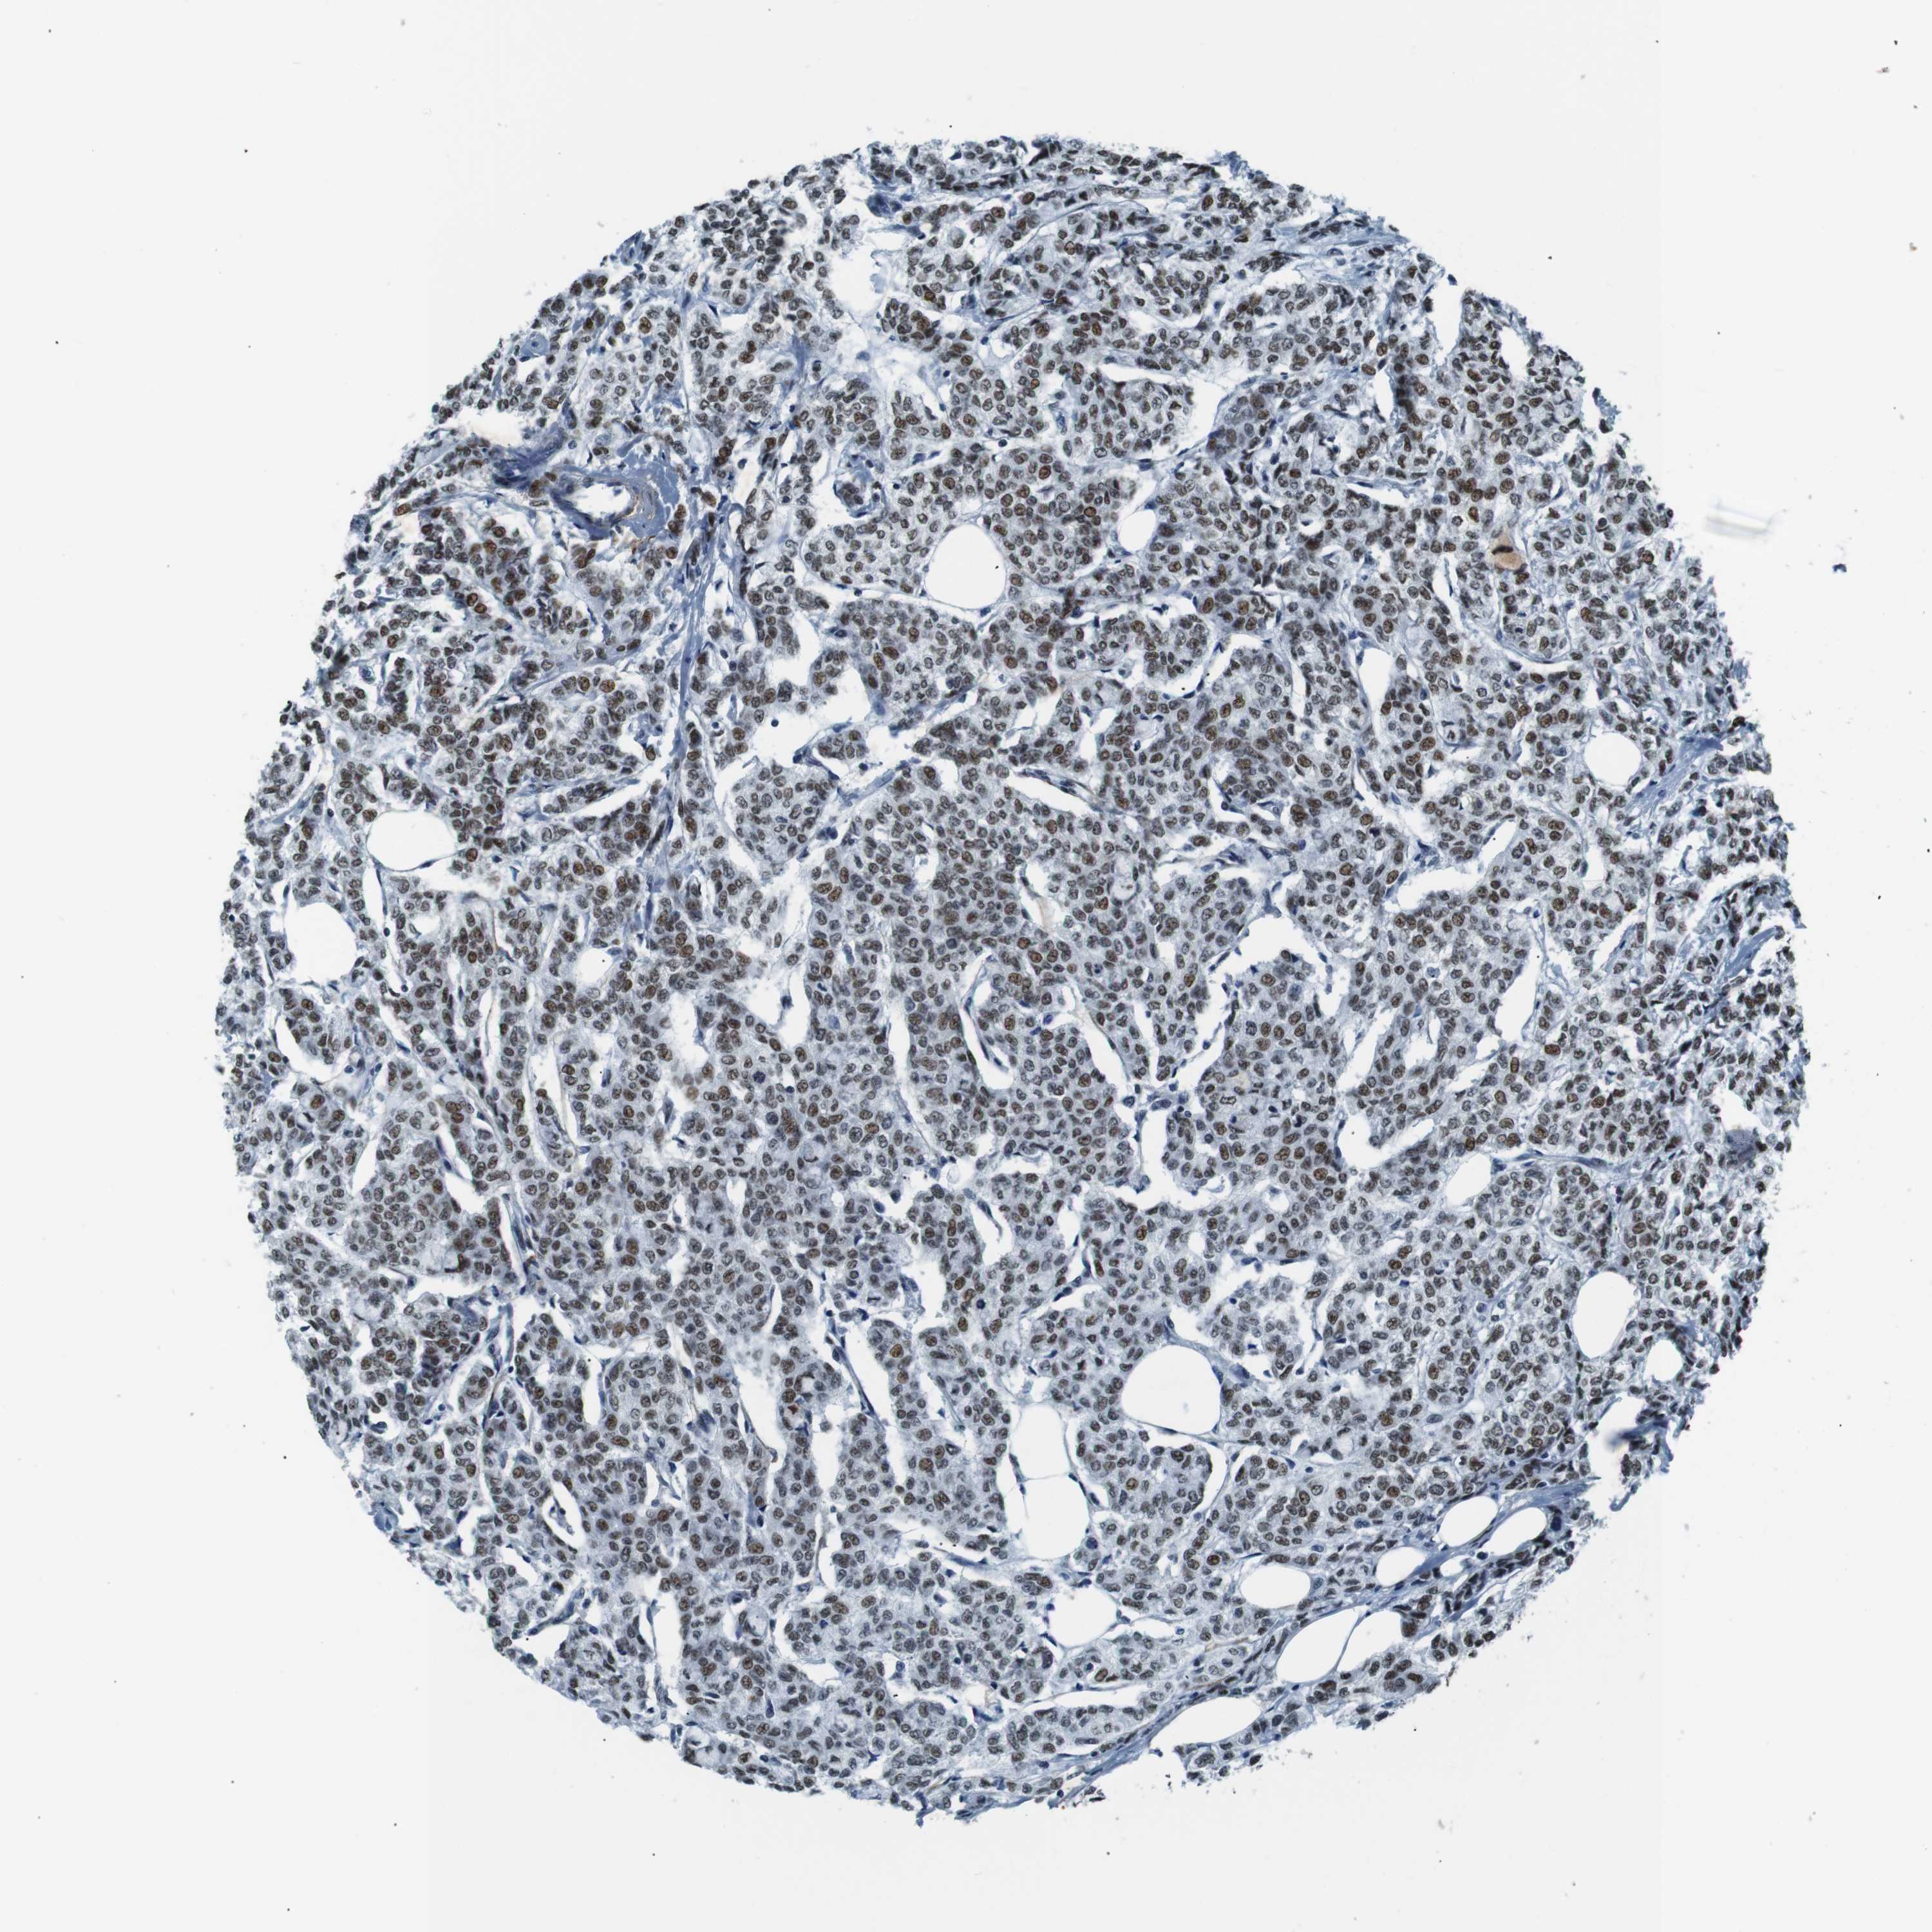

CANCER BREAST CANCER Show tissue menu

BRCA TCGA BRCA VALIDATION PROTEIN EXPRESSION